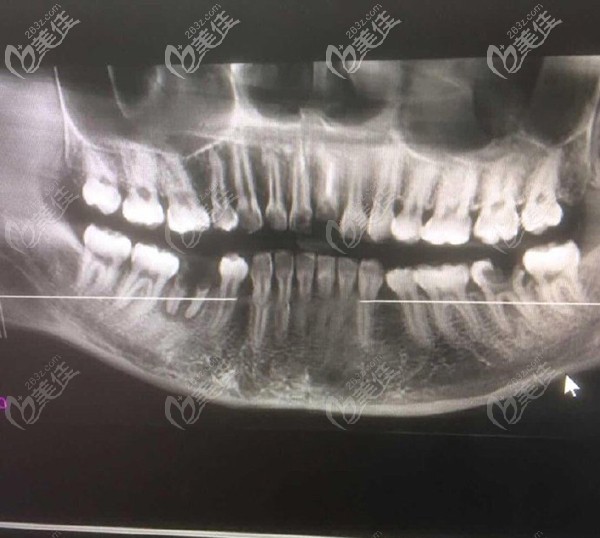

問題是本寶寶還不止缺一顆牙,只不過在我看來門牙尤為重要,來院后,醫(yī)生大概看了牙齒情況后,建議還是拍個CT看看,以便于確認(rèn)給我更好的方案。

放大看看更清楚

【牙齒情況】:門牙缺失一顆,下半口缺失一顆,但是有殘根。